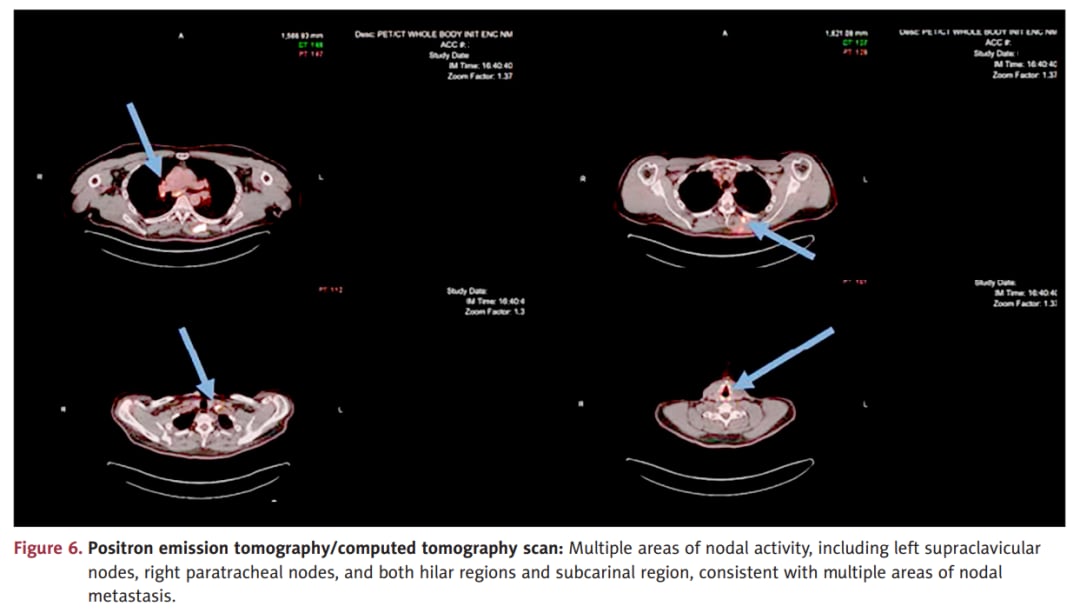

PET/CT可帮助识别淋巴结和骨转移,是分期与疗效评估的重要工具。

一旦PET/CT或其他影像提示淋巴结、骨或远处脏器转移,疾病管理目标通常会从“根治性切除”转向“全身控制+症状缓解”。对于高级别上皮样血管肉瘤,这个转折尤其重要,因为它的自然病程往往更快。

- 区域或远处淋巴结转移